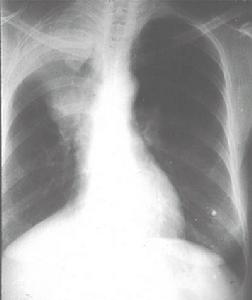

脫屑性間質性肺炎 X線表現,兩肺有對稱性磨玻璃模糊陰影,在肺底部最顯著。亦有呈三角形模糊陰影,從肺門向兩側肺底伸展,有時並發自發性氣胸或胸水。

脫屑性間質性肺炎 X線表現兩肺有對稱性磨玻璃模糊陰影在肺底部最顯著亦有呈角形模糊陰影,從肺門向兩側肺底伸展有時並發自發性氣胸或胸水。

肺功能檢查顯示限制型改變伴DLCO降低,動脈血氣顯示低氧血症。胸部X線在多達20%病例可正常,如有異常時,其嚴重程度低於間質性肺纖維化。HRCT示斑片狀,胸膜下的毛玻璃樣陰影。經支氣管鏡或開胸作肺活檢,可以確定診斷。

肺功能檢查顯示限制型改變伴DLCO降低,動脈血氣顯示低氧血症。胸部X線在多達20%病例可正常。如有異常時,其嚴重程度低於間質性肺纖維化。HRCT示斑片狀,胸膜下的毛玻璃樣陰影。